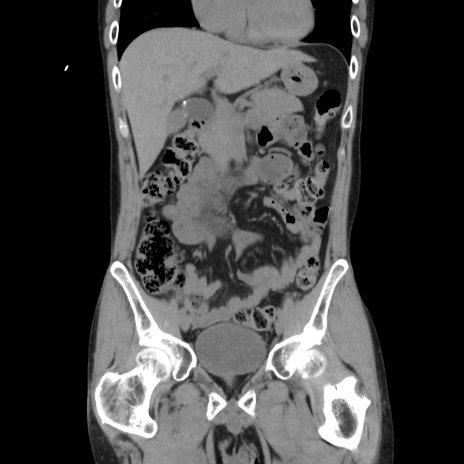

横断像

【症例】40歳代 男性

【主訴】腹痛

【現病歴】4時間ほど前に電車に乗車中に臍部上より腹痛出現。徐々に増悪し起立困難となり、救急外来受診。生ものは数日食べていない。今朝お雑煮を食べた。

【身体所見】BT 36.8℃、BP 117/84mmHg、HR 91/min、SpO2 97%、苦悶様、腹部:臍上部広範囲圧痛あり、反跳痛±

【データ】WBC 8100、CRP 0.03